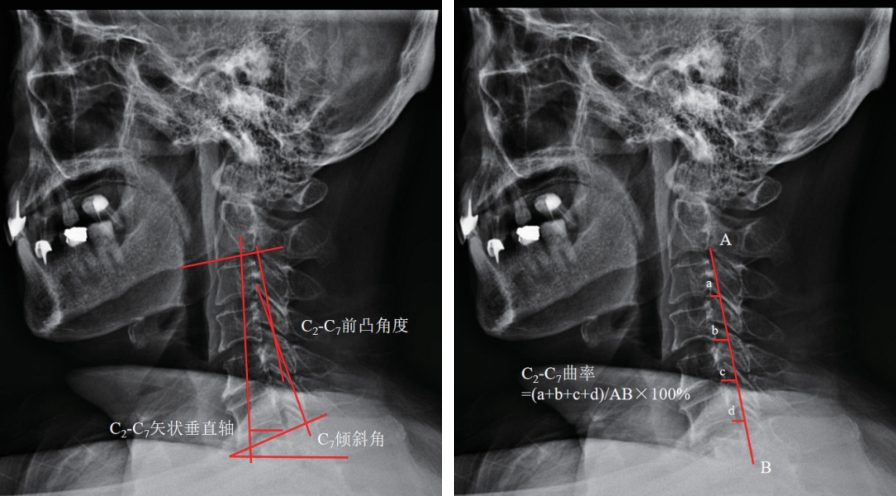

• 脊髓型颈椎病椎板成形术后颈椎前凸丢失的影响因素分析

2025, 35(19):99-104. DOI: 10.3969/j.issn.1005-8982.2025.19.016

摘要 (116) HTML (20) PDF 927.37 K (47) 评论 (0) 收藏

摘要:目的 分析脊髓型颈椎病(CSM)椎板成形术后颈椎前凸丢失的影响因素。方法 选取2022年1月—2025年1月沧州市中心医院123例CSM患者作为研究对象。根据术后前凸丢失情况分为前凸严重丢失组(35例)与无前凸严重丢失组(88例)。收集所有患者性别、年龄、体质量指数、病程等基线资料及颈椎矢状面参数,并对两组进行比较。采用多因素一般Logistic回归模型分析CSM患者术后颈椎前凸丢失的影响因素。结果 前凸严重丢失组与无前凸严重丢失组的性别、年龄、体质量指数、病程、手术节段数、手术入路、合并高血压、合并糖尿病、颈痛及骨密度分类构成比较,差异均无统计学意义(P >0.05)。前凸严重丢失组患者的C2或C7累及、术前前凸角度(CL)、C7倾斜角、C2-C7曲率及屈曲活动范围较无前凸严重丢失组高(P <0.05)。前凸严重丢失组与无前凸严重丢失组的术前颈椎对齐情况、术前手术节段CL、CSVA、伸展活动范围比较,差异均无统计学意义(P >0.05)。多因素一般Logistic回归分析结果显示:累及C2或C7[O^R=6.465(95% CI:1.544,27.074)]、术前CL大[O^R=1.404(95% CI:1.215,1.621)]、C7倾斜角大[O^R=1.299(95% CI:1.144,1.476)]、C2-C7曲率高[O^R=3.323(95% CI:1.488,7.423)]、屈曲活动范围大[O^R=2.117(95% CI:1.584,2.830)]均为CSM患者术后前凸严重丢失的危险因素(P <0.05)。结论 CSM患者颈椎损伤累及C2或C7时,在椎板成形术后出现颈椎前凸严重丢失;同时患者的颈椎矢状面参数包括术前CL、C7倾斜角、C2-C7曲率及屈曲活动范围更大时,术后也更易出现颈椎前凸严重丢失。

• 0+1